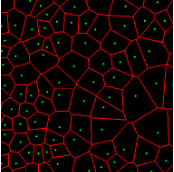

In practice, directly using point annotation for the nuclei segmentation could suffer from the data-imbalance problem due to insufficient supervision information. To alleviate this issue, we adopt the Voronoi diagram [24] and the k𝑘k-means clustering method [25] to generate Voronoi label and cluster label, respectively. Specifically, for Voronoi labels, as shown in Fig. 1, the image is divided into convex polygons based on the point annotations with the assumptions that the point labels are at the nuclei centers and nuclear shapes are convex (even though these assumptions are not necessarily valid). For cluster labels, as shown in Fig. 1, we utilize the k𝑘k-means to obtain more supervision information of nuclei boundary and shape as follows. First, we calculate the distance maps from the point labels by performing distance transform between each pair of points. Second, the distance maps are combined with the original H&E stained images to conduct the k𝑘k-means clustering to divide all pixels into k=3𝑘3k=3 clusters: nuclei, background, and ignored area. The clusters that have maximum and minimum overlap with the point annotations are labeled as nuclei and background, respectively. The remaining one is the ignored class. The introduction of an ignored area allows pixels that cannot be easily determined as nuclei or background with certainty not be forced into either class, ensuring that the clustering can assign correct pixel labels as much as possible [27]. Third, several morphological operations are adopted to refine the cluster label, including connected domain labeling, scattered region removing, morphological opening operation, and binary hole filling.

where visubscript𝑣𝑖v_{i} and cisubscript𝑐𝑖c_{i} denote the Voronoi label and cluster label of nuclei at the i𝑖i-th pixel, respectively; y=S(xh)𝑦𝑆subscript𝑥y=S(x_{h}) denotes the prediction of the segmentation network S𝑆S with H-component xhsubscript𝑥x_{h} as input; and ΩsubscriptΩ\Omega_{*} (i.e., ΩvsubscriptΩ𝑣\Omega_{v} or ΩcsubscriptΩ𝑐\Omega_{c}) is the set of non-ignored pixels. As illustrated in Fig. 1, the Voronoi label is used to supervise the network to separate overlapping nuclei, while the cluster label could provide coarse shape and boundary information for nuclei segmentation. In the following, we elaborate the co-training strategy to further provide supervision to the ignored area of the coarse cluster labels, denoted with the blue color in Fig. 1.